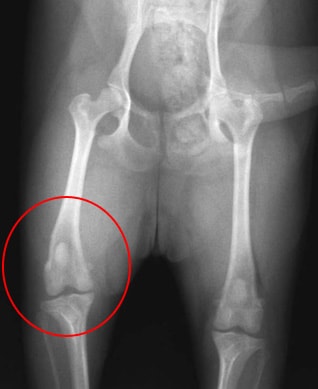

膝蓋骨脱臼

膝蓋骨とは膝のお皿の事で、このお皿の骨が脱臼することを膝蓋骨脱臼といいます。

チワワやトイプードル、ミニチュアダックスフンドなどの小型犬種に多く発症し、

主に内側へ脱臼します。膝蓋骨脱臼には重症度の分類がなされており、グレード1からグレード4まで様々あります。高グレードの膝蓋骨脱臼では痛みを伴い、また、脛骨変形や半月板損傷、膝関節炎が起こり、跛行の原因となります。

高グレードの膝蓋骨脱臼では通常外科的整復手術が必要となるケースが多いです。

当院では、出来る限り膝への負担が少ない手術方法「S-K法」を用いて手術を行っております。

![]() 膝蓋骨脱臼を起こしているレントゲン写真 |

![]() S-K法にて整復手術した後のレントゲン写真 |